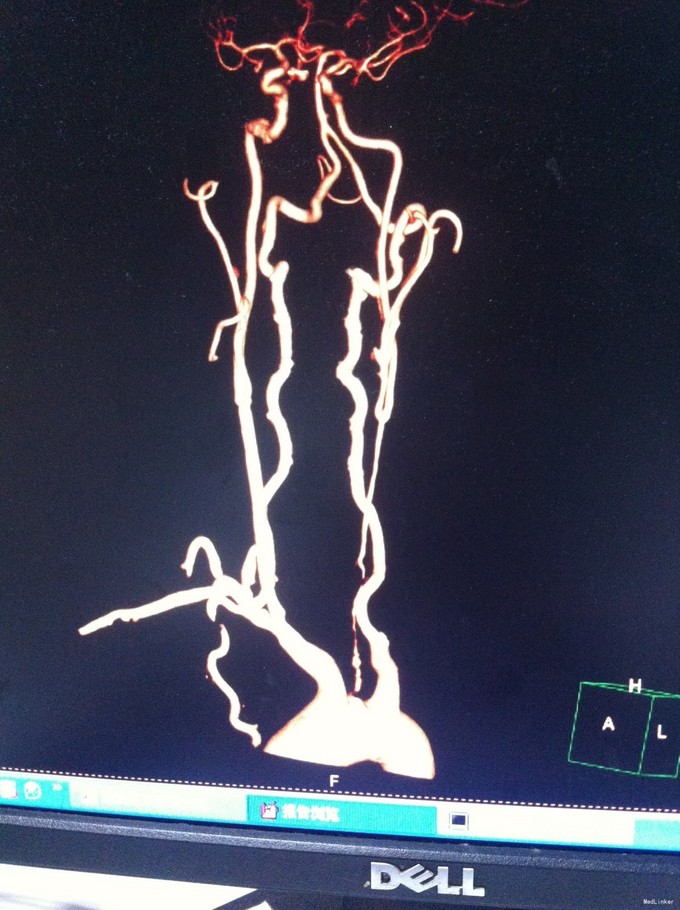

颈总动脉全程狭窄病例一例

动脉狭窄 颈总动脉狭窄

1、眩晕综合征 2、左侧颈总动脉狭窄

随访:该患者拟每三月复查头颈部动脉CTA,定期复查血脂、血糖、血压等情况。目前使用双抗加立普妥治疗。 讨论:患者颈总动脉狭窄、可否行支架植入治疗,个人觉得不可取,请各位专家多提宝贵意见,谢谢。